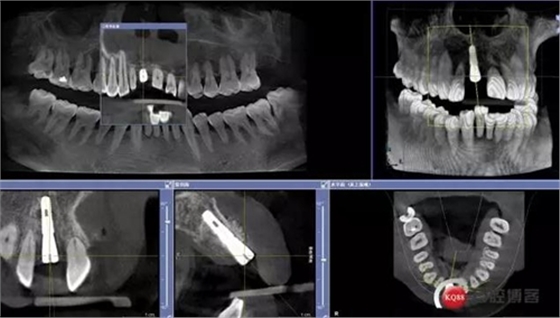

患者:王XX 年齡:42 上前牙松動數(shù)年,從未做過任何處理,今來院就診;檢查:CBCT示上前牙區(qū)顎側(cè)一大小約7x7mm囊腫;治療計劃:即刻種植同期摘除囊腫

術前CBCT